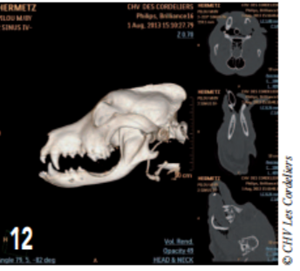

L’ostectomie allait en profondeur jusqu’au canal mandibulaire (photos 9 à 12).

Photo 12 : Reconstruction en 3D du crâne en postopératoire.

L’ostectomie n’ayant pas créé de discontinuité entre la partie articulaire de la mandibule et la symphyse, il n’y a aucune malocclusion.